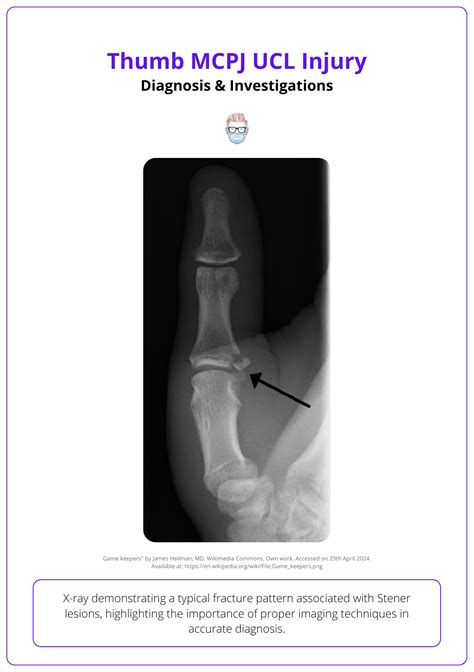

To determine if you are suffering from a ruptured ulnar collateral ligament, a medical professional will conduct a physical examination and utilize advanced imaging. The doctor will perform a "valgus stress test," where they apply gentle pressure to the outside of the elbow while the arm is slightly bent to see if there is excessive laxity or reproduction of pain.

X-ray Ruling out bone fractures or loose bodies in the joint.